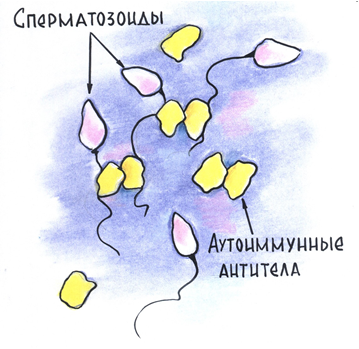

В случаях, когда организм мужчины сам вырабатывает антиспермальные антитела, их называют аутоиммунными (греч. auto — «сам собой»). Аутоиммунные антитела прикрепляются прямо к сперматозоидам (рис. 5). Из-за этого они начинают склеиваться между собой, теряют способность к передвижению.

Рис. 5. Схема действия аутоиммунных антител